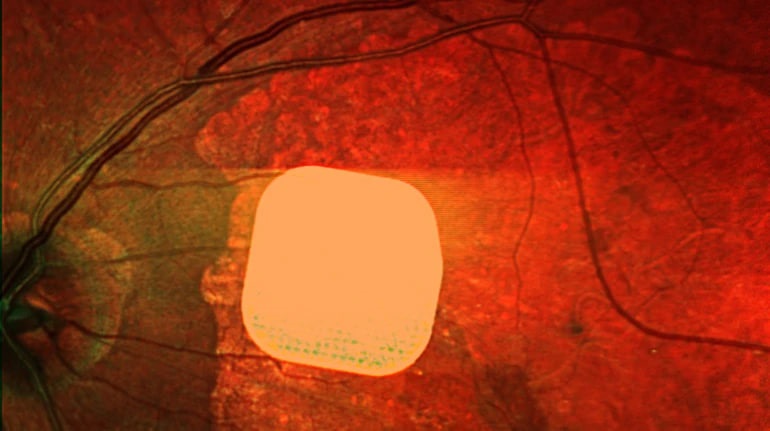

Британські лікарі частково повернули зір пацієнтам за допомогою мікрочипа

Британські лікарі успішно випробували новий електронний імплант Prima, який допомагає частково відновити зір у пацієнтів…